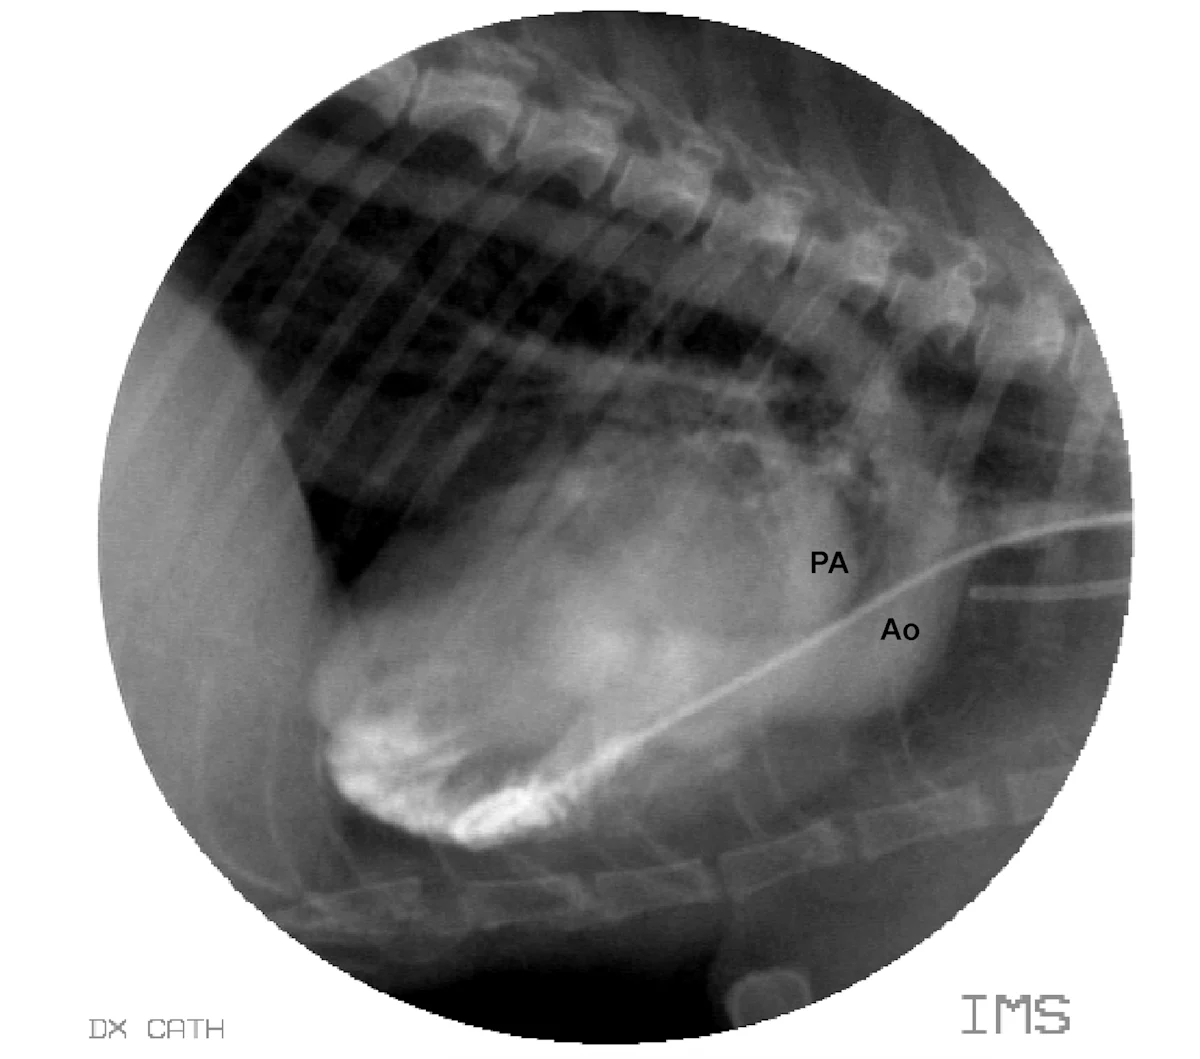

Central cyanosis occurs when the circulating blood has more than 5 g/dL of hemoglobin desaturated of oxygen. This can be seen in animals with clinically significant pulmonary disease and hypoxemia or with right-to-left cardiovascular shunts, such as a reverse patent ductus arteriosus and tetralogy of Fallot (Figure B). This right ventricular angiogram demonstrates blood flow from the right ventricle into the aorta (Ao) and pulmonary artery (PA) in a cat with tetralogy of Fallot.